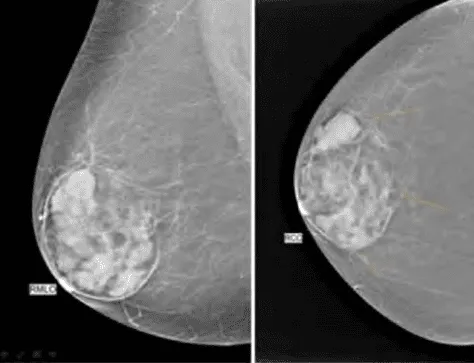

Phần tiêu đề “Cận lâm sàng”Hình ảnh “Bướu diệp thể: Khối lớn, rõ, có các vùng hóa nang và thùy. Nhũ ảnh cho thấy vôi hóa không đồng nhất, siêu âm thể hiện khe rãnh và hóa nang”.

Siêu âm:

- Khối giảm âm, bờ rõ, có thể có các vùng hóa nang (cystic spaces) phân bố rải rác.

- Gợi ý phẫu thuật ngay nếu khối lớn, tăng sinh mạch máu bất thường.

Nhũ ảnh: Khối lớn, giới hạn rõ, có thể bầu dục, hình tròn hoặc chia thùy, thỉnh thoảng thấy vôi hóa (ít phổ biến hơn fibroadenoma).

MRI: Thần kinh hóa mô đệm rõ, khối đồng nhất hoặc có vùng thoái hóa, bắt thuốc mạnh - thường dùng trong khối nghi ngờ ác tính hoặc khối tái phát.